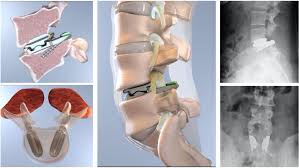

Isthmic Spondylolisthesis

Pars interarticularis is a very strong pillar of bone which acts as a stabilizing staructure or lock between spinal bones. Sometimes, this pars interarticularis develops a break or defect due to which the spine loses its stability resulting in slippage of one bone on another. The reason for this pars defect may be injury, repeated injury over a period of time as in sportspersons / athletes or due to anatomical predisposition since birth. This type is most common at L5-S1.

How is Spondylolisthesis Surgery done?

This operation is done from the back. In this operation, titanium screws are inserted in 2 spinal bones and the disc between them is taken out in entirety while protecting the spinal nerves. Then, a plastic cage filled with bone graft is packed in the place of the disc so that over a period of time, bone grows between the two bones and they become fused (joined) to each other. This eliminates any further risk of slipping and relieves the patient’s pain.